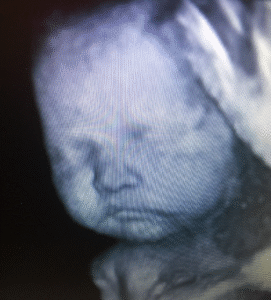

If you are an expected mother and anxious to get a glimpse of your new creation, 3D4D Imaging Center can make it happen. You will be able to see activities of your baby inside the womb which is difficult or impossible to identify with traditional scanning.

Baby Faces

20 Weeks – 30 Weeks

Includes 8-10 3D pics and watching baby move in 3D (4D), confirmation of Gender.